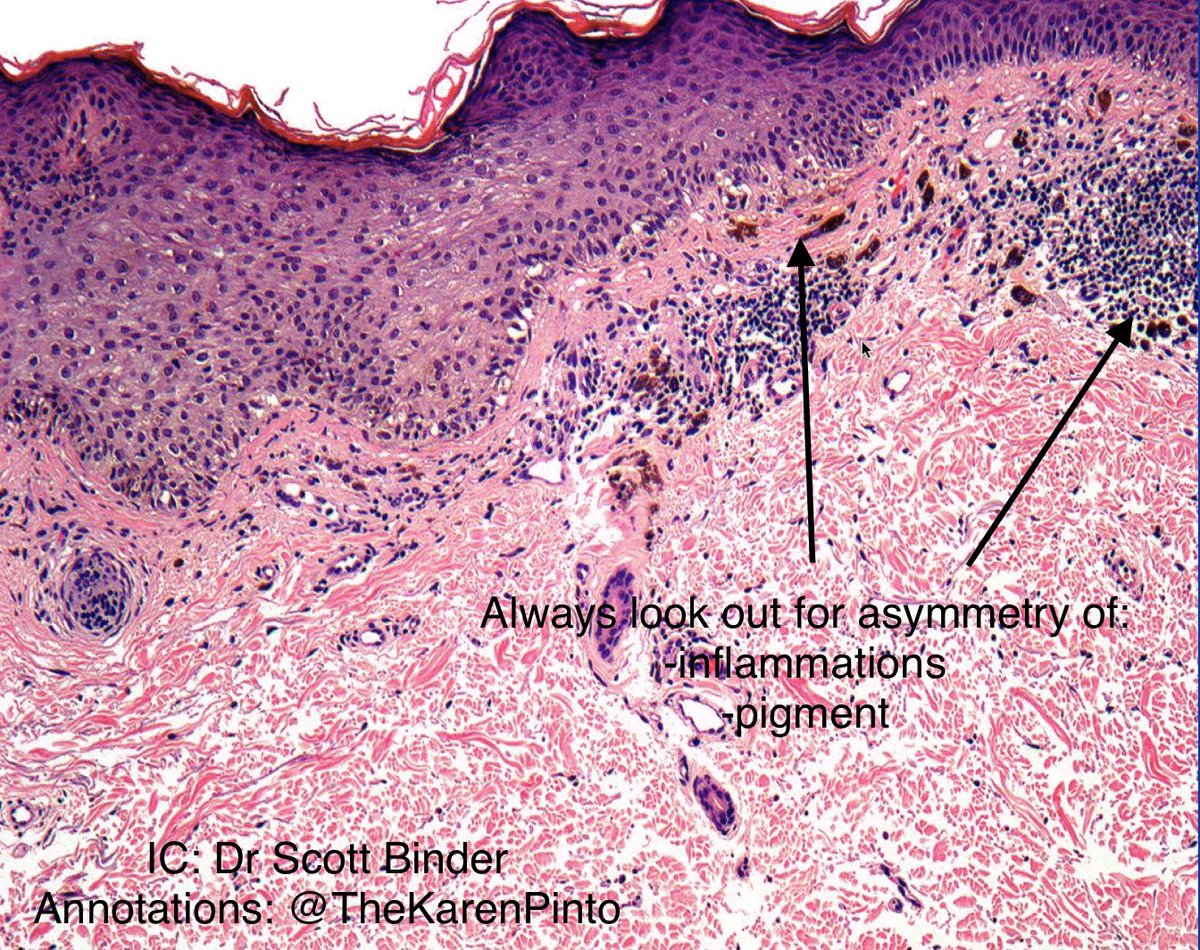

⁉️#GUpath #PEDIpath⚠️ 15YOB with a 7 mm intra testicular nodule... 🔪GROSS🔪 Woo Cheal Cho, MD GU Pathology Society (GUPS) Dr.Gauri Vidolkar MD Frank Ingram, MD Ankur Sangoi @evacomperat Daniel Skipper @AkgulMd Jonathan Zuckerman MD PhD Carla Ellis MD, MS Erasistrate Farshid Siadat, MD, FRCPC Francesca Khani, MD Peter Sadow, MD, PhD Ashish M. Kamat, MD, MBBS Nature Reviews Urology ⏭

It is unknown time! What is your guess? Make sure to follow Willy Kemp for more teaching treasures!